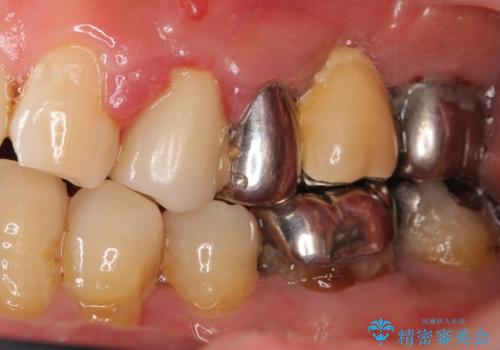

- 左上の歯ぐきが腫れていることを主訴に来院された患者様です。

精査したところ、歯ぐきが腫れている左上の小臼歯(左上4)は保存不可能な状態でした。

インプラント・ブリッジ・入れ歯の選択肢を提案させて頂いたところ、ブリッジをご希望されました。

保存不可能な歯(左上4)を抜去後、ブリッジによる補綴治療を行いました。